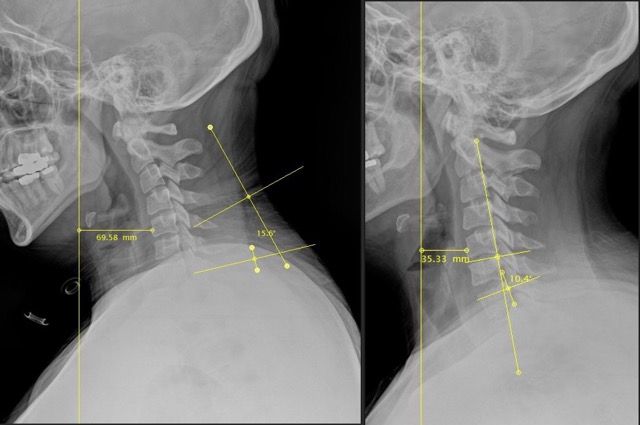

We use detailed X-rays to measure the exact position of your head in relation to your spine. This gives us a clear starting point and allows us to track your improvement with objective measurements.

We take follow-up X-rays to show you exactly how your spine is changing. The images don't lie - you'll see real structural improvement, not just temporary relief.

Our before and after X-rays show dramatic improvements in neck curve and head positioning. What many people think is a permanent problem can actually change with the right care.